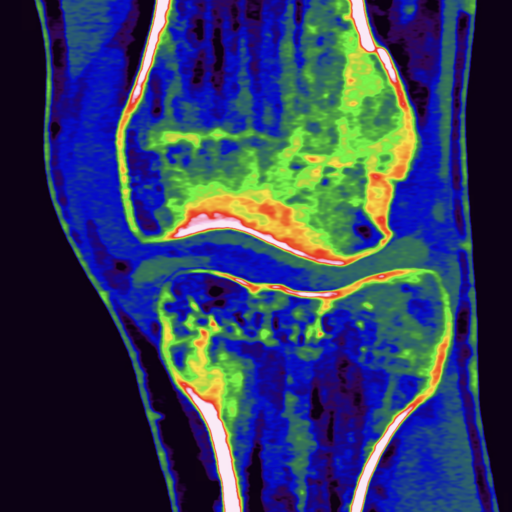

comparison of the the images 60, keV monoenergetic, virtual non-contrast (VNC), and iodine map images. The repercussion starts in the proximal tear of the intimate (the first three images), calcification in the intimate (next three images), tera at the level of the arising intercostal artery (last three images)

comparison of the sagittal aortic MPR in 40, 60, 140 and 190 keV monoenergetic images

comparison of the perpendicular planes to sagittal aortic MPR in 40, 60, 140 and 190 keV monoenergetic images